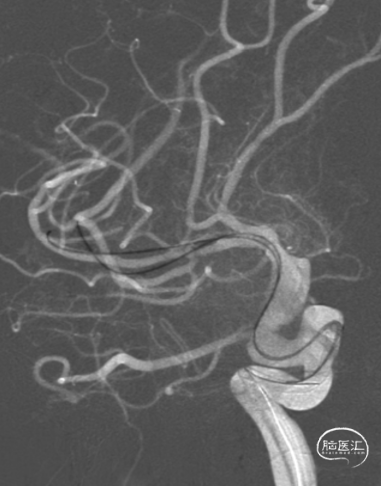

TRUST技术,6F 105cm Tethys®中间导引导管+5F 125cm Simmons 2+260cm 软泥鳅导丝建立通路。

Tethys®中间导引导管内衬5F 125cm Simmons 2+260cm软泥鳅经锁骨下动脉,Simmons 2至降主动脉,回撤导丝,弓上成袢后,先超选至右侧颈总动脉,解袢充分释放张力。

Simmons 2勾选目标动脉,跟进导管,开始建立通路,Tethys®中间导引导管稳定在通路中。

Connect 300cm V18导丝内支撑,2根200cm snychro-2微导丝分别超选至M2上下干。

1.5*10mm 球囊先扩下干,并造影,可见局部狭窄明显改善。

术后影像

术后CTA。

术后CTP。